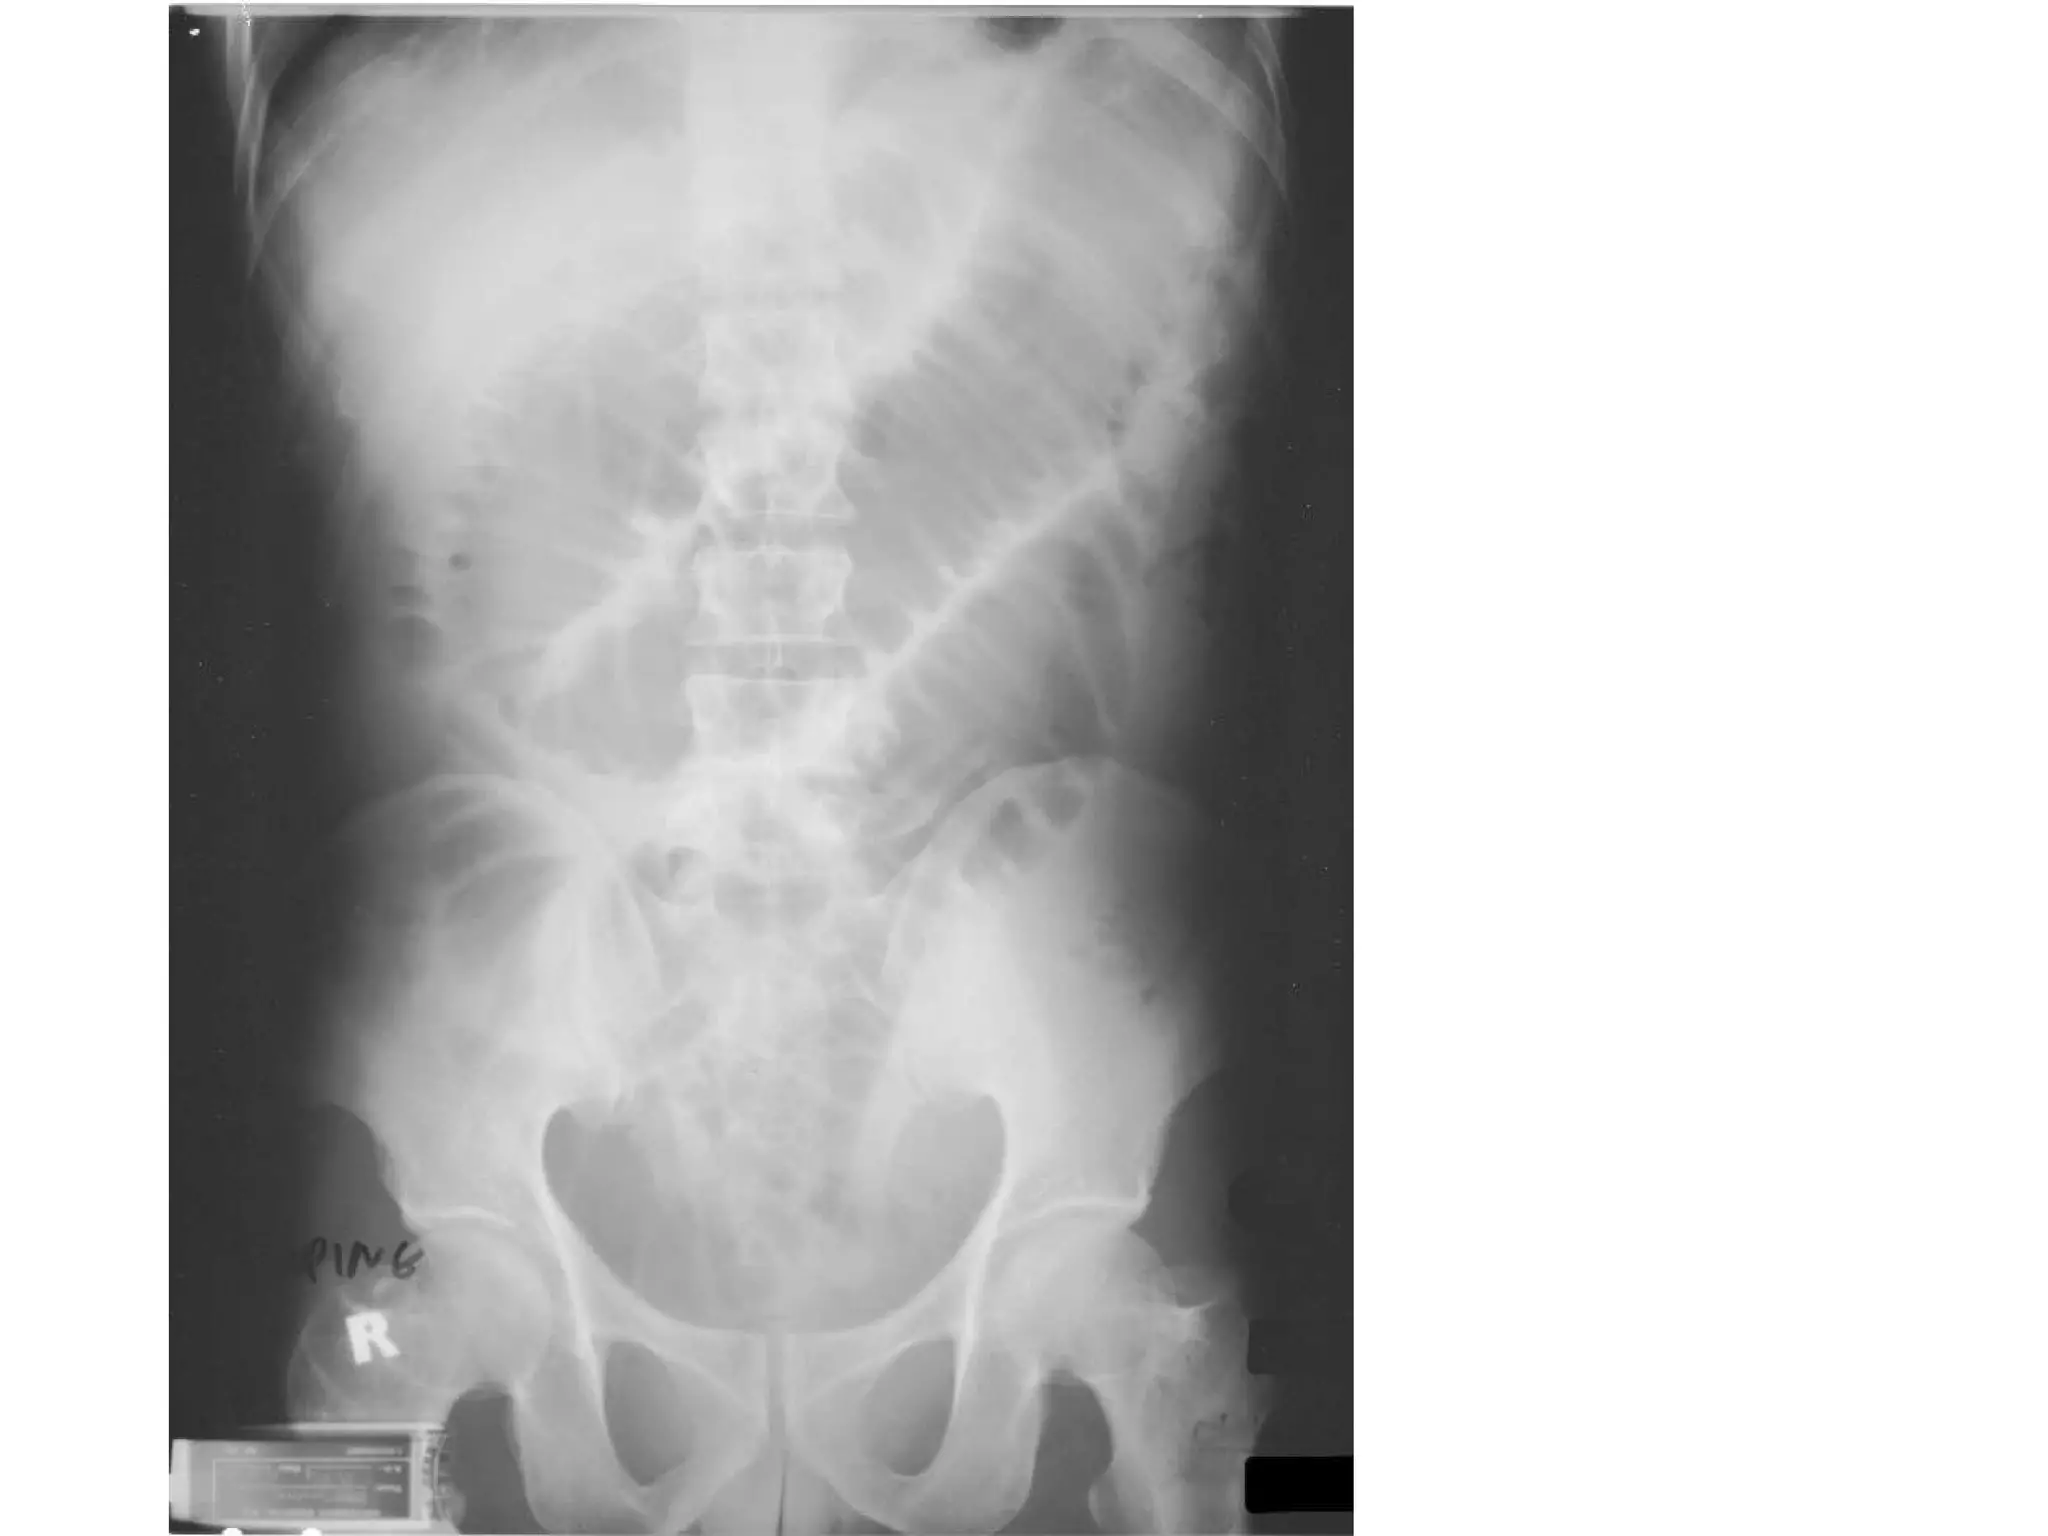

AXR- small bowel obstruction Describe? Ladder pattern of dilated loops Central position Striations complete across width of loops (valvulae conniventes/circular mucosal fold) >3cm <5cm Causes? Luminal: fecal/food, gallstone ileus, pedunculated tumour Intramural: congenital atresia, tumour, Crohn’s dz, diverticulitis Extramural: strangulated hernia, volvulus/intussusception, adhesion/banding 2 S&S? Vomiting Abd pain Abd distension constipation Vs large bowel: Peripheral Haustrations of taenia coli >5cm

Presented with abd distension, vomiting

AXR- intestinal obstruction 3 abnormalities? Dilated bowel Multiple air fluid level (normal <4) Paucity of air distal to obstruction Dx? Intestinal obstruction 2 causes? Adhesion/banding Tumour (pedunculated/intramural)

AXR- small bowelobstruction Describe? Ladder pattern of dilated loops Central position Striations complete across width of loops (valvulae conniventes/circular mucosal fold) >3cm <5cm Causes? Luminal: fecal/food, gallstone ileus, pedunculated tumour Intramural: congenital atresia, tumour, Crohn’s dz, diverticulitis Extramural: strangulated hernia, volvulus/intussusception, adhesion/banding 2 S&S? Vomiting Abd pain Abd distension constipation Vs large bowel: Peripheral Haustrations of taenia coli >5cm

Presented with abddistension, vomiting

AXR- intestinal obstruction3 abnormalities? Dilated bowel Multiple air fluid level (normal <4) Paucity of air distal to obstruction Dx? Intestinal obstruction 2 causes? Adhesion/banding Tumour (pedunculated/intramural)